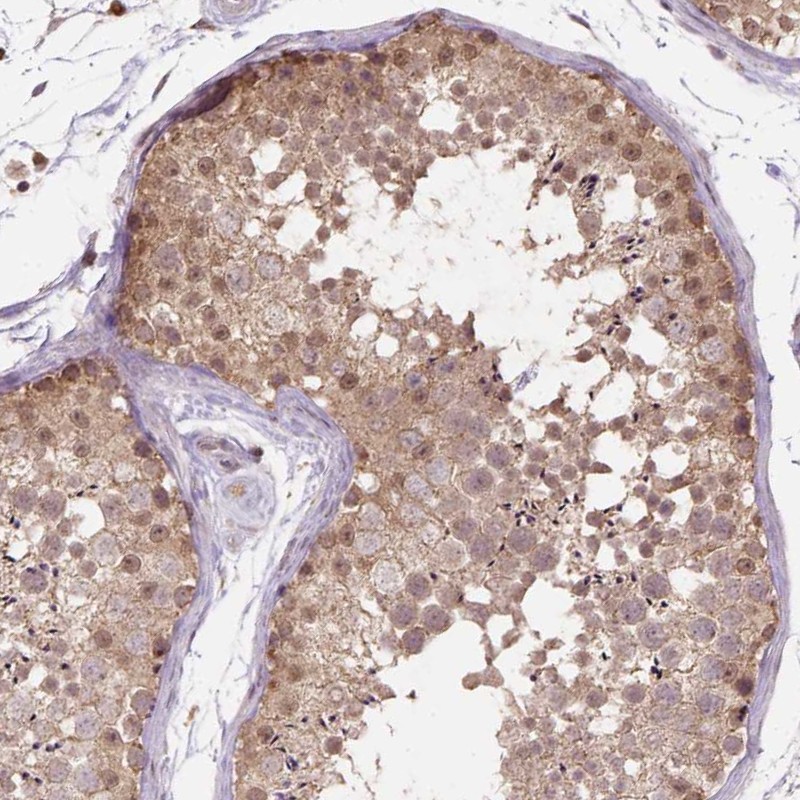

Immunohistochemical staining of human testis shows moderate cytoplasmic and nuclear positivity in cells in seminiferous ducts.